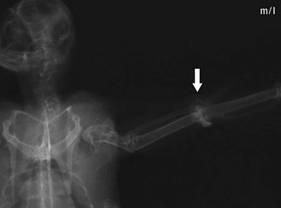

Wrist luxation: in

the mediolateral radiation duct

there seems to be

only slight damage, which could be overlooked |

Wrist luxation:

the extent of the damage can only be

seen with the

caudocranial radiation duct |